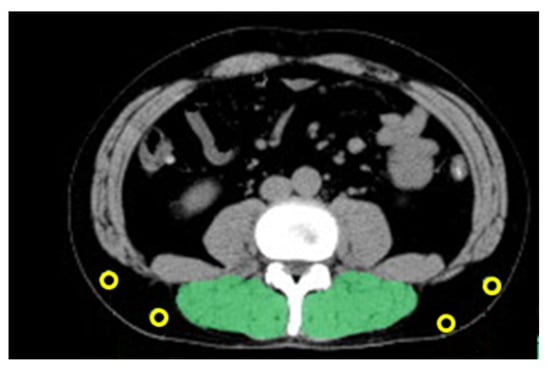

2.4. Measurements of PMI and IMAC

3.2. Measurement of the PMI and IMAC